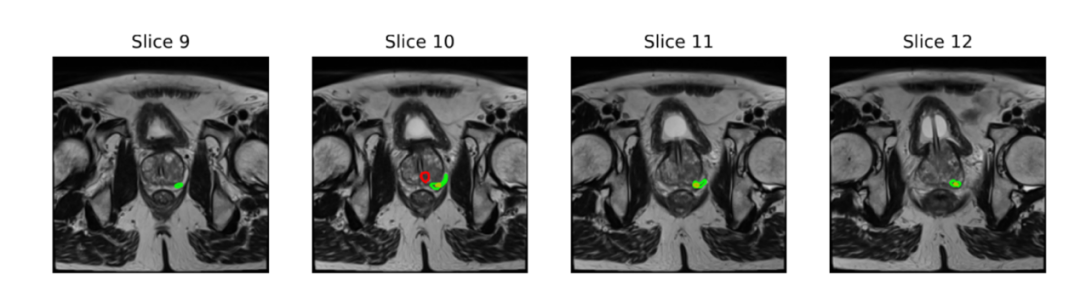

图丨病灶标注对比示例:人类专家(红色轮廓)、AI(黄色轮廓)与数据集中的专家标注(绿色轮廓)(来源:arXiv)研究结果首先证实了 AI 辅助的直接价值,但也揭示了一个更深层次的协作瓶颈。在第一组实验中,放射科医生独立诊断的平均准确率为 63.2%,获得 AI 辅助后,他们的平均准确率提升至 66.2%。然而,这一“人+AI”的协作表现,仍未能超越 AI 模型本身 69.3% 的独立诊断准确率。